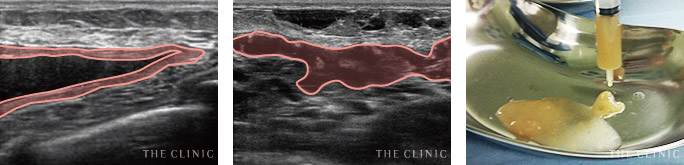

実際のエコー画像

-

施術前

アクアフィリング豊胸のしこりが散在し、一部は塊に -

溶解中

エコー下でしこりにアプローチし、確実に生理食塩水を注入 -

除去したアクアフィリング

完全に溶解しないケースでも、エコー下できれいに吸引除去